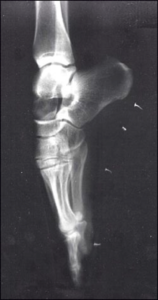

Top – X-ray of a foot on pointe. http://7.159.220.196/diamond_pointe.shtml